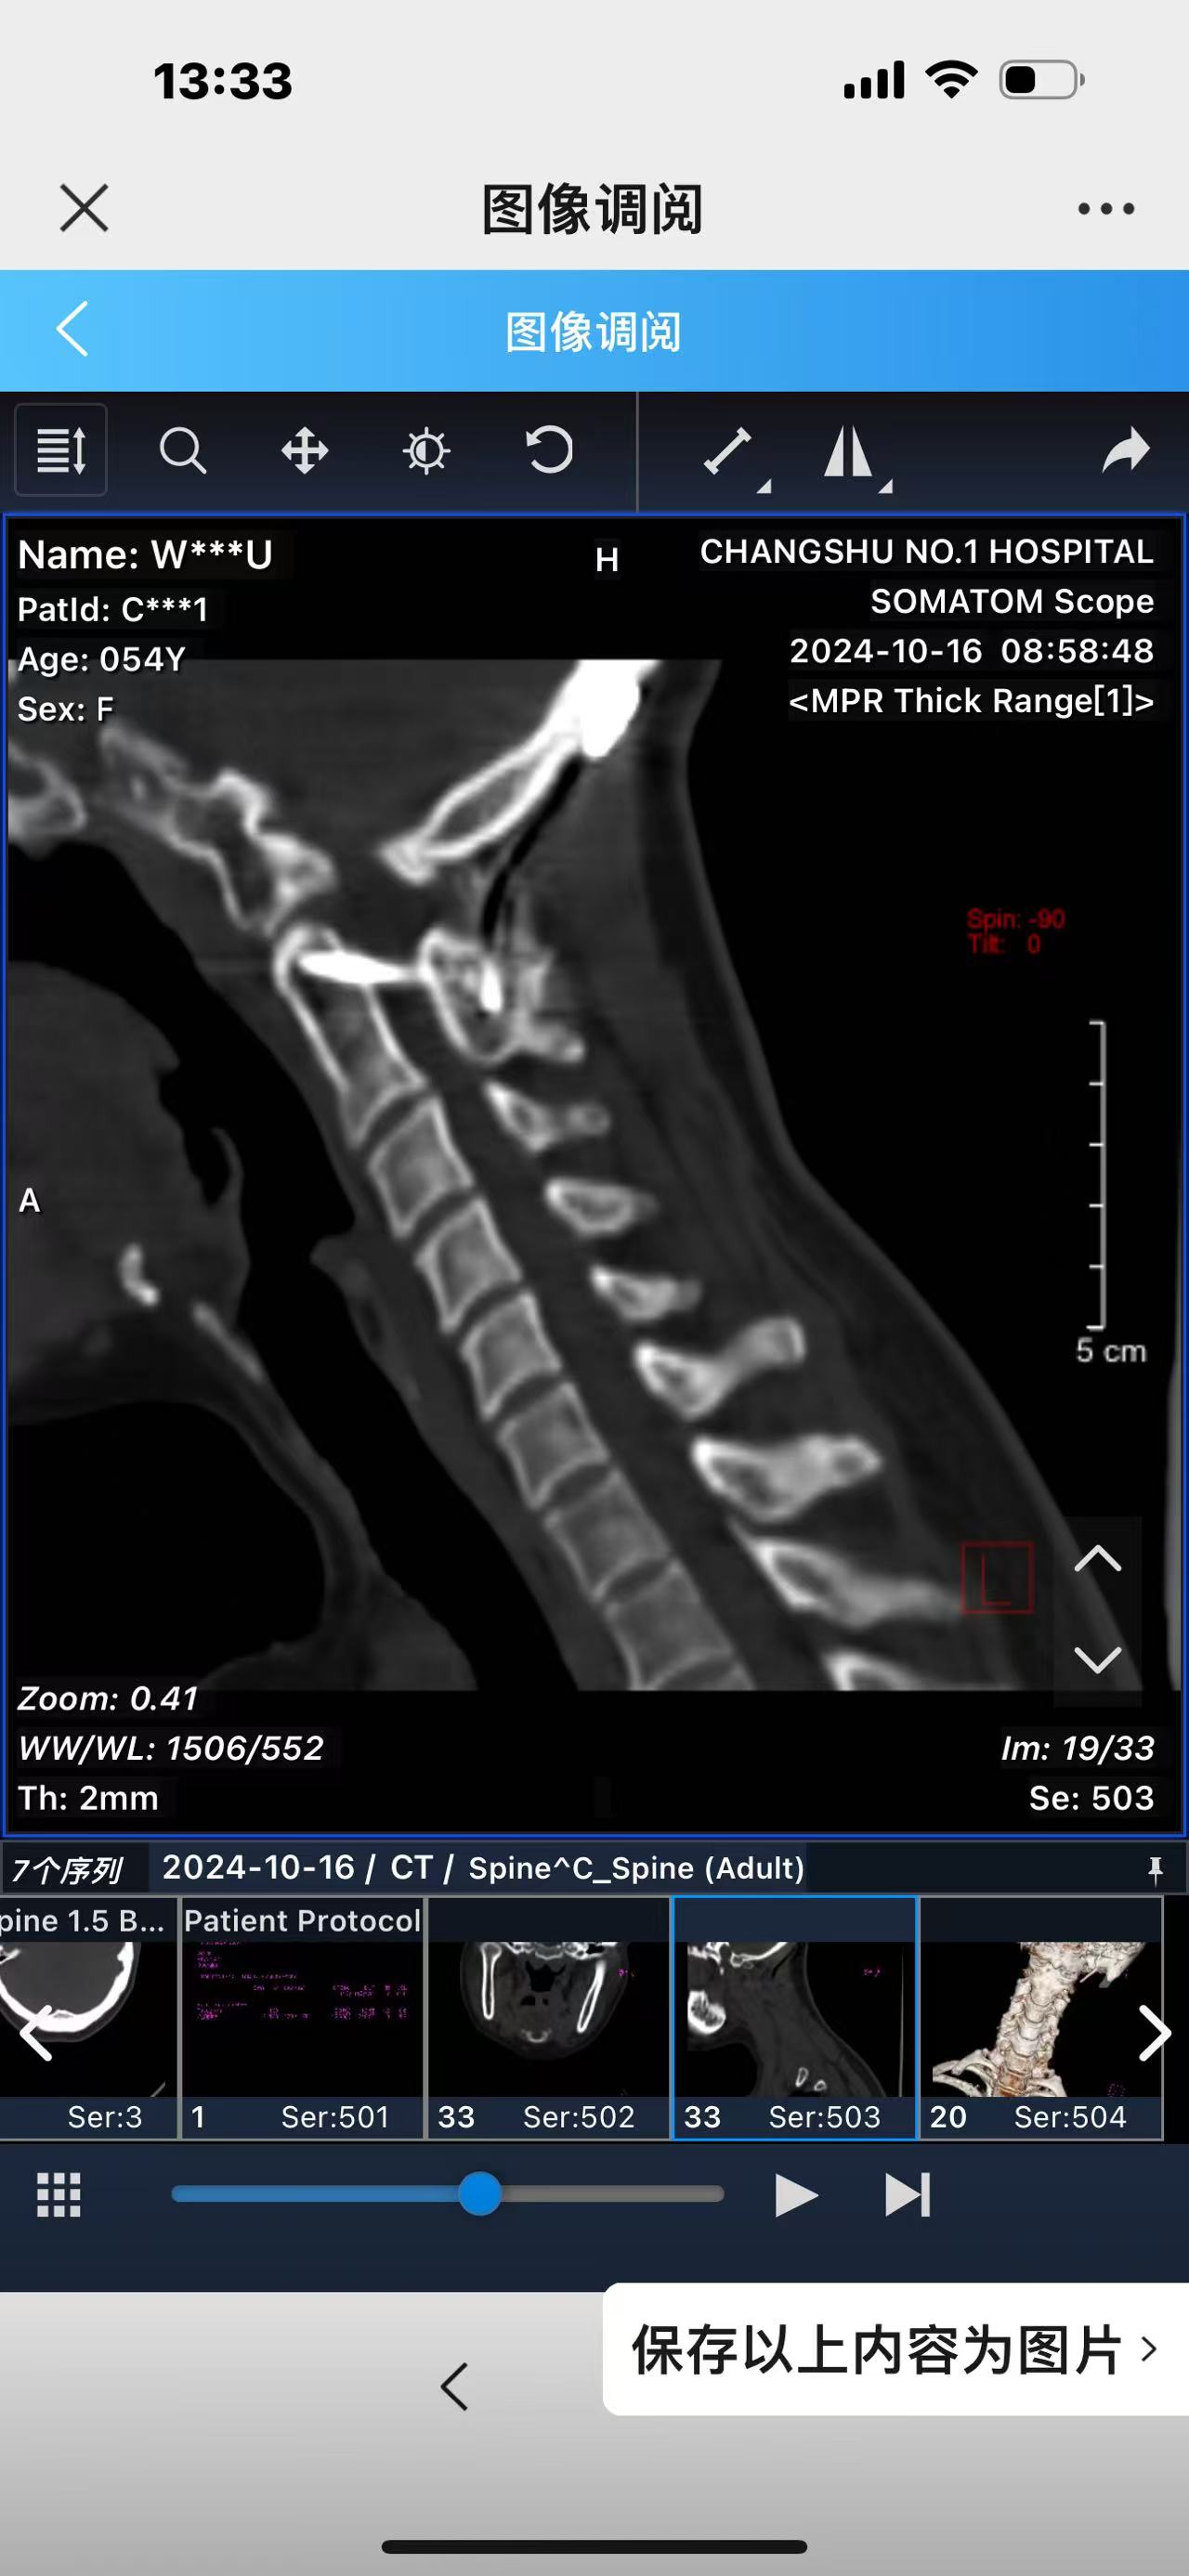

• 诊断:寰枢椎脱位,颅底凹陷

• 2024.10.20,复查,对位良好,偶尔会肩甲骨酸,坐下就不酸。